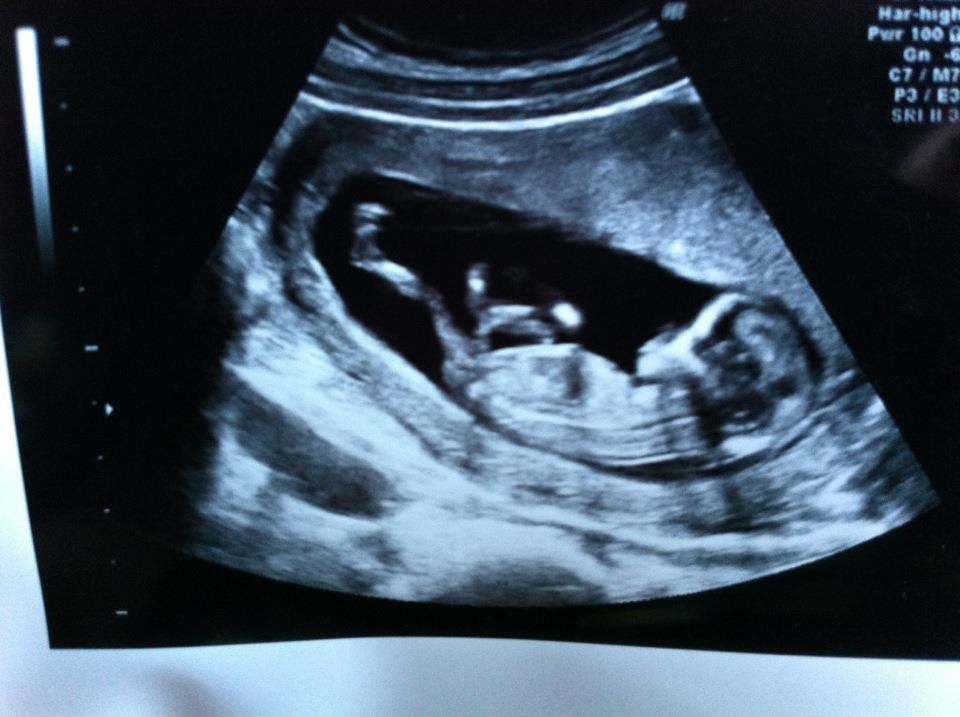

Vi har været igennem en moderkagebiopsi, da vi var i risikozonen for at vores barn ville have down syndrom.

Men nogen dage efter fik vi et brev hvori der stod at vi ventede en sund og rask dreng